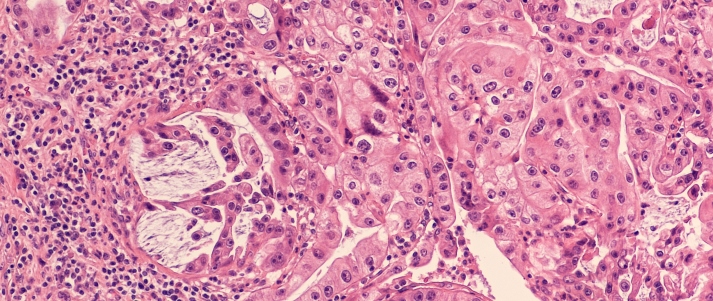

UofG scientists to lead multimillion pound research project into bowel cancer treatments